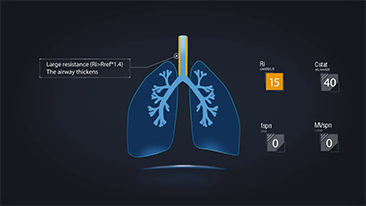

La elecciĂłn de la configuraciĂłn correcta del respirador para el tratamiento de pacientes con enfermedades de las vĂas respiratorias es un asunto muy importante. Dado que un mĂ©dico es responsable de la tarea de especificar los parĂĄmetros del equipo de ventilaciĂłn en su totalidad, el conocimiento y la experiencia del mĂ©dico en la selecciĂłn de estos ajustes tiene un efecto directo en la precisiĂłn de sus decisiones. El paradigma de la atenciĂłn de apoyo de los pacientes ha cambiado significativamente durante los Ășltimos 20?a?os. Hoy en dĂa, se han desarrollado varios modos de ventilaciĂłn y herramientas de apoyo de la toma de decisiones en torno a las necesidades clĂnicas para ayudar a los profesionales a mejorar la eficiencia y eliminar errores en estas decisiones.

Al integrar la oxigenoterapia de alto flujo, la ventilaciĂłn no invasiva y la ventilaciĂłn invasiva, los respiradores 3?en?1 de la serie?SV combinan un desempe?o estable, funciones versĂĄtiles y facilidad de uso. Las excepcionales caracterĂsticas de protecciĂłn pulmonar y las numerosas herramientas de apoyo de la toma de decisiones se dise?aron para reducir el riesgo de infecciĂłn cruzada y facilitar el trabajo diario de los profesionales.